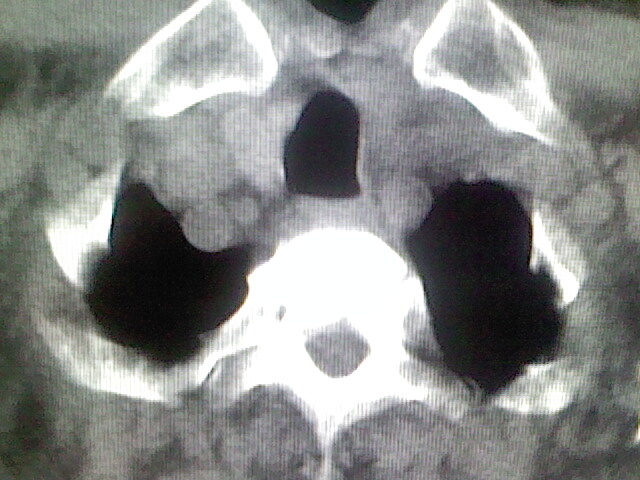

以下是引用zsl6918在2008-8-28 16:49:00的发言:[br]双肺炎性病灶,食管狭窄估计与心房增大压迫所致。

以下是引用xulianj在2008-8-28 20:36:00的发言:[br]慢支肺气肿伴感染,右上肺陈旧性结核;食道建议胃镜检查。

以下是引用wqs571018在2008-8-28 21:18:00的发言:[br]慢支继发感染,右上肺陈旧性结核;食道建议胃镜检查。